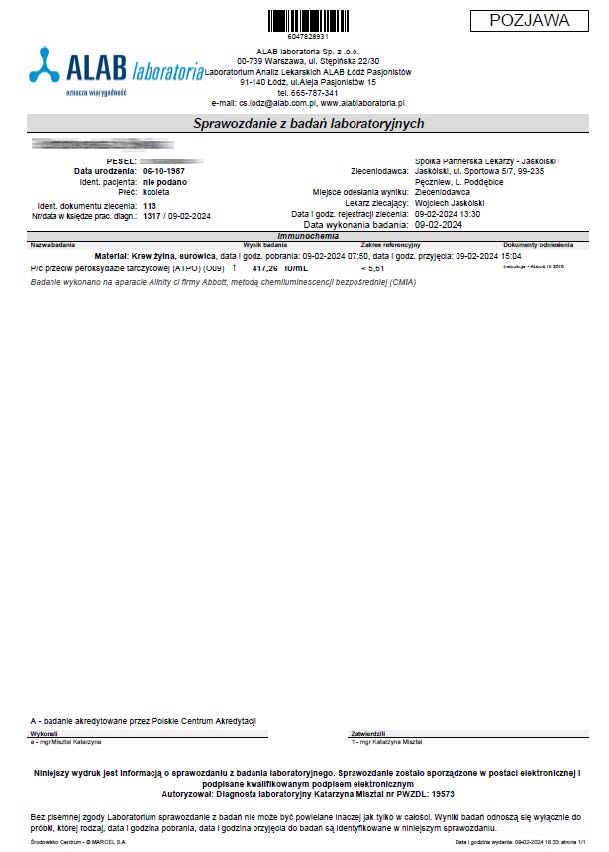

PRZYKŁAD EFEKTU PREPARATU NA NIEDOCZYNNOŚĆ TARCZYCY

Kobieta lat 59 z niedoczynnoscią tarczycy, bez przyjmowania lewotyroksyny. Kobieta przyjmowała preparat przez okres ponad 3 miesięcy. Przy zachowaniu naturalnego cyklu komórkowego i stałemu stymulowaniu mitochondriów osiągneła następujące wyniki kuracji:

Po zaobserwowaniu znacznej poprawy w ogólnym samopoczuciu, kobieta postanowiła wykonywać badania ze zwiększoną częstotliwością oraz kontrolę prób wątrobowych.

Po kolejnych dwóch miesiącach kobieta ponownie wykonała badania. Widoczne są: spadek TSH, obniżenie stanu zapalnego jak i spadek markeru wątrobowego GGTP.

Sukcesywnie co 2 miesiące można zaobserwować stały spadek parametrów zarówno wątroby jak i tarczycy. Kolejne badania potwierdzały dalszy spadek parametrów.

Po ponad roku kuracji badania wykazały dalszy postęp wycofania autoimmunologi tarczycy, potwierdzone również badaniem USG narządu.

Preparat wpływając na odbudowę mitochondriów zapewnił podłoże energetyczne do produkcji hormonów i odbudowy narządu. Brak ingerencji farmakologicznej wykazuje skuteczność nawet w podeszłym wieku, gdzie regeneracja jest wolniejsza a reakcje anaboliczne w znacznym stopniu spowolnione. Można zaobserwować także działanie ogólnoustrojowe obserwując spadek markeru wątroby, co jasno wykazuje poprawę funkcjonowania całego organizmu.

Kobieta lat 36 zastosowała terapię preparatem ze względu na pogarszające się samopoczucie i wysoki wynik TSH oraz anty-tpo jednoznacznie wskazujący na niedoczynność tarczycy. Brak zastosowanej farmakologii lewotyroksyną. Po zaledwie 12 dniach stosowania preparatu odnotowano znaczny spadek parametrów tarczycy oraz przeciwciał.

Wyniki odwrócenia procesów autoimmunologicznych wykraczają poza typowe leczenie i wykazują, że preparat wzmacnianjąc i stymulując mitochondria działa poprzez energetyczną optymalizację, co umożliwia długoterminową regenerację w różnych grupach wiekowych.